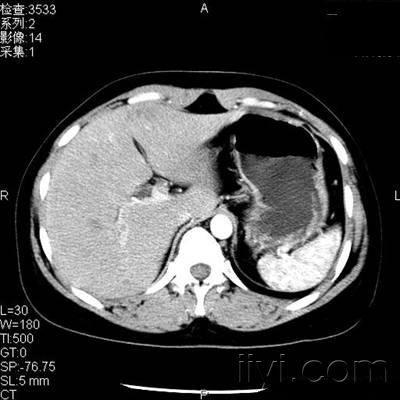

患者,女性,体检发现肝左叶低密度病变2天

[ 本帖最后由 梅雪 于 2009-1-16 08:45 编辑 ] 动脉期